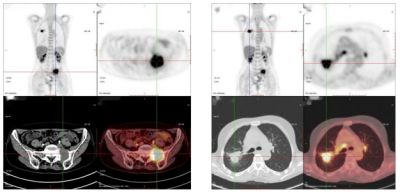

40歲,女,外院查腫瘤標(biāo)志物示:癌胚抗原(CEA)411.00 ng/ml,糖類抗原19-9(CA19-9)30.0 U/ml;來我科行PET/CT檢查。

PET/CT診斷:乙狀結(jié)腸癌伴肝臟、淋巴結(jié)多發(fā)轉(zhuǎn)移;隨后病理確診為乙狀結(jié)腸腺癌。